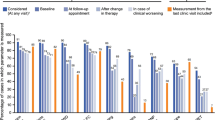

As risk-assessment strategies excluding RHC parameters performed well at baseline, we tested the clinical usefulness and predictive value of the FPHR3p and mRASP at follow-up. In line with the aforementioned clinical and functional improvement following treatment initiation, patients shifted from higher to lower risk categories (Fig. 3). Notably, with both risk models, major improvements were mainly seen between baseline and the first follow-up, whereas at third and fourth follow-up risk strata distribution remained roughly unchanged.

Mortality risk stratification according to the FPHR3p and mRASP risk assessment tools at baseline and follow-up. Risk assessment according to the three-parametric FPHR and mRASP risk stratification tools. The percentage of the total for each risk category is depicted. Nbaseline = 130, N1st follow-up = 112, N2nd follow-up = 103, N3rd follow-up = 93, N4th follow-up = 87